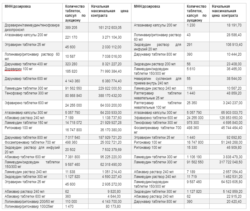

Мнение эксперта подтверждает отчет группы "Здравресурс" о закупках АРВТ в 2023 году в РФ (вошли также данные с сайта "Перебои.ру"), согласно которому на второй год войны бюджет на закупку антиретровирусных препаратов уменьшился почти на треть (в сравнении с 2022 годом).

"На снижении бюджета сказалось и то, что в 2022 году потратили часть бюджета 2023 года. В итоге объемы практически всех закупленных препаратов сократились, – пишет экспертный ресурс. – Всего было объявлено 144 аукциона, но заключили контракты только по 89 из них. По оставшимся 55 не было предложений от поставщиков. Практически все препараты, по которым торги не состоялись, имеют зарегистрированные дженерики от отечественных фармпроизводителей, которые при этом не выходят на торги. Вероятной причиной отсутствия заявок на аукционы является установленная ФКУ ФЦПиЛО начальная максимальная цена контракта (НМЦК), которая значительно ниже по сравнению с аналогичными закупками 2023 года. Общая сумма несостоявшихся аукционов составляет 2,16 млрд рублей. В то же время контракты на сумму 15,22 млрд рублей уже заключены".

– Например, торги на "Ламивудин" 300 мг, "Атазанавир" 300 мг, "Зидовудин" 300 мг, "Абакавир" 240 мл состоялись только с третьего раза, – заявили активисты "Здравресурса".